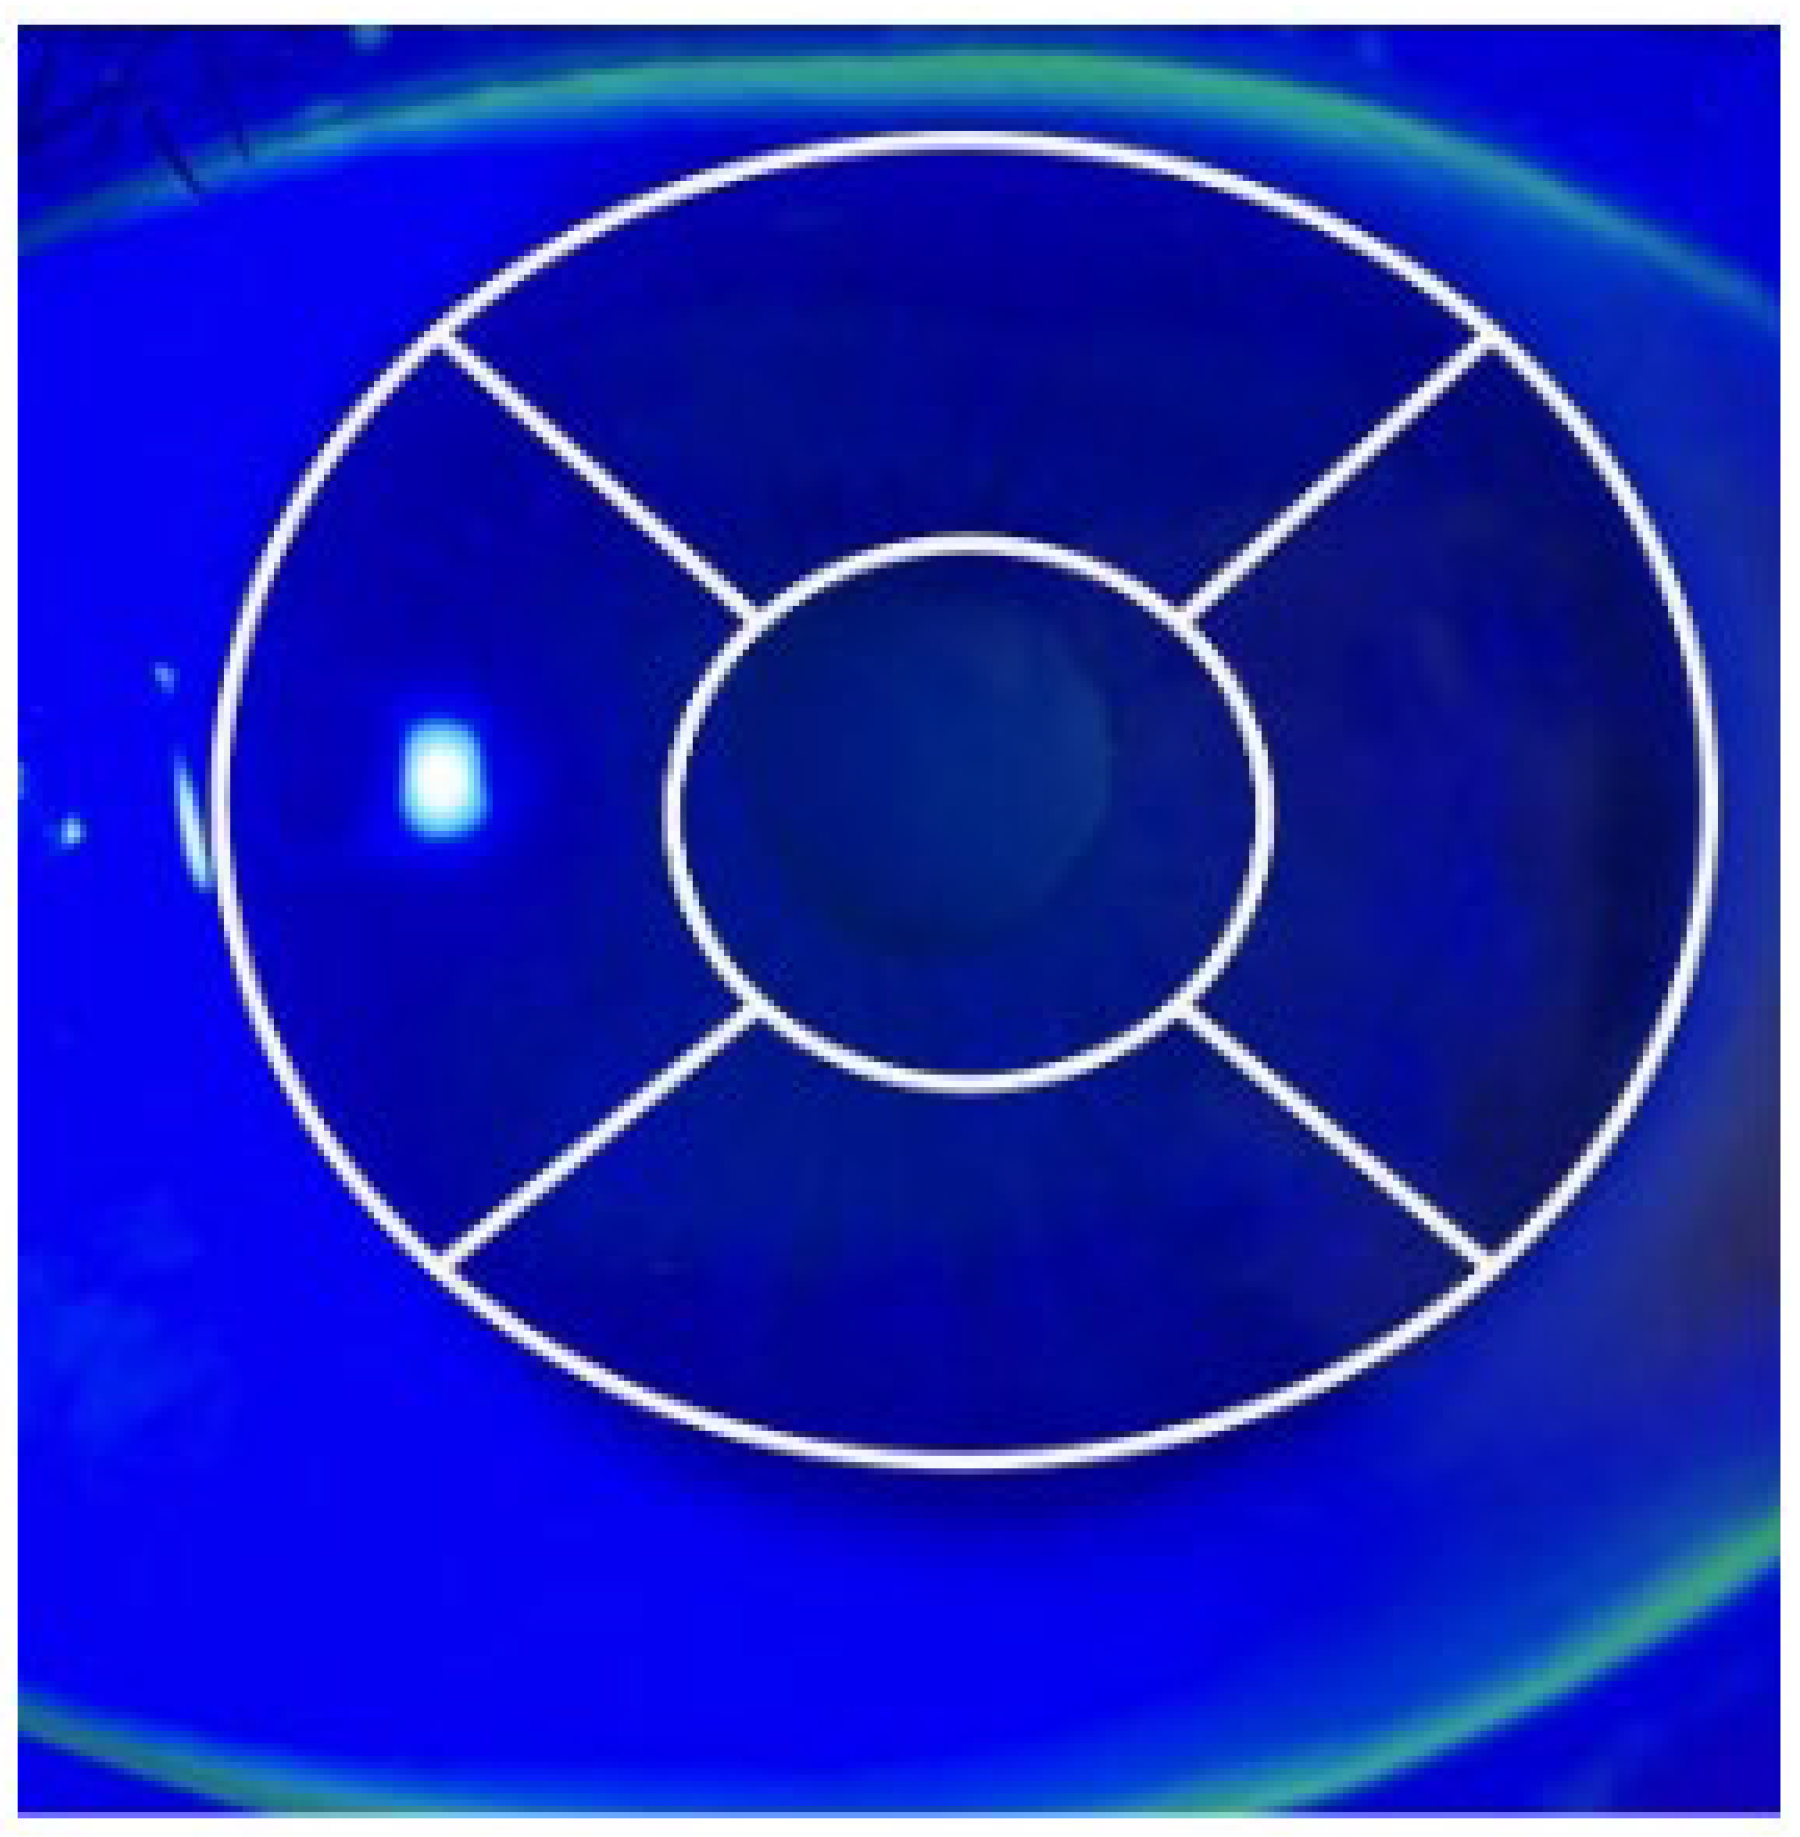

The corneal fluorescence staining score was calculated for each case by dividing the cornea into five areas (central, inferior, superior, nasal, and temporal) based on the National Eye Institute reference (Figure 1). Each area was graded as follows: no staining (0 points), mild staining (1–15 punctate stains = 1 point), moderate staining (16–30 punctate stains = 2 points), and severe staining (≥30 punctate stains = 3 points). The points for all areas were summed to obtain the corneal staining score (CSS) for each eye [9].

Figure 1.

Corneal image showing the division of the cornea into five zones (central, superior, nasal, inferior, and temporal) for scoring corneal staining, as defined by the National Eye Institute.